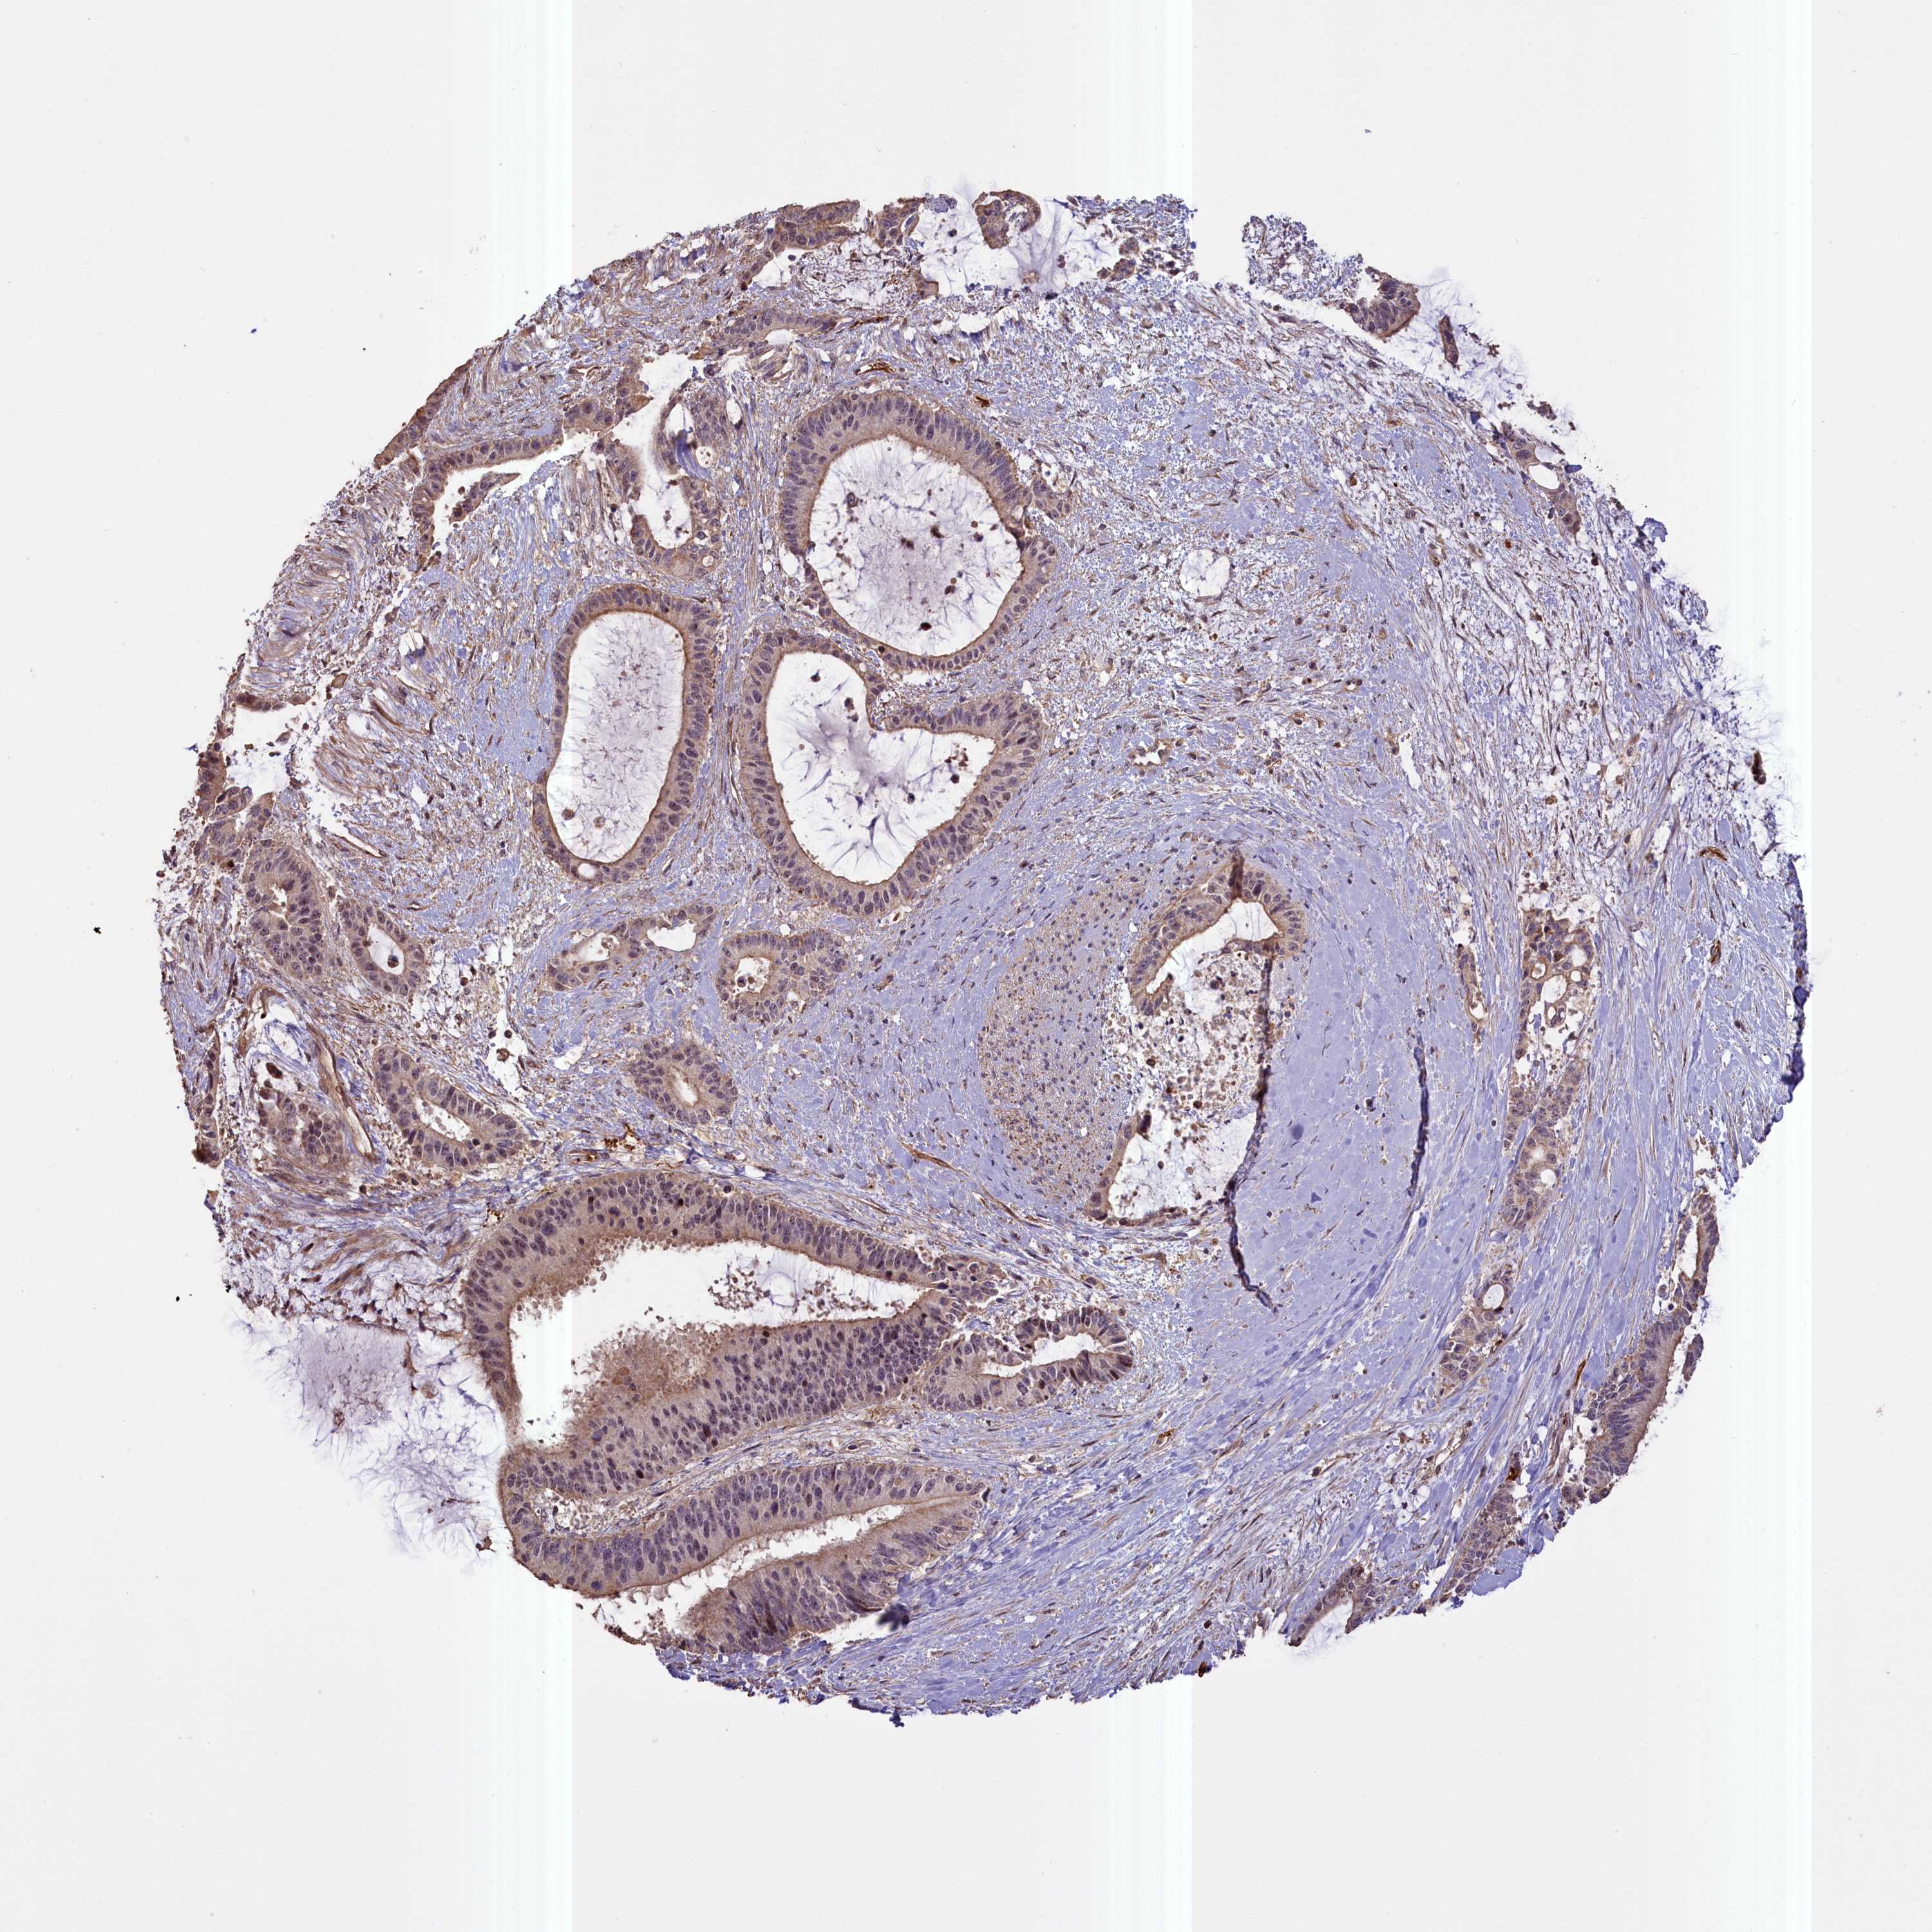

LIVER CANCER - Protein expressioni

A mouse-over function shows sample information and annotation data. Click on an image to view it in a full screen mode. Samples can be filtered based on level of antibody staining by selecting one or several of the following categories: high, medium, low and not detected. The assay and annotation is described here.

Note that samples used for immunohistochemistry by the Human Protein Atlas do not correspond to samples in the TCGA dataset.

Antibody stainingi

Antibody staining in the annotated cell types in the current human tissue is reported as not detected, low, medium, or high, based on conventional immunohistochemistry profiling in selected tissues. This score is based on the combination of the staining intensity and fraction of stained cells.

Each image is clickable and will lead to virtual microscopy that enables deeper exploration of all samples and also displays staining intensity scores, fraction scores and subcellular localization as well as patient and tissue information for each sample.

Antibody HPA041779

Antibody HPA042196

Staining

High

Medium

Low

Not detected

Intensity

Strong

Moderate

Weak

Negative

Quantity

>75%

75%-25%

<25%

None

Location

Nuclear

Cytoplasmic/membranous

Cytoplasmic/membranous,nuclear

Cholangiocarcinoma

Carcinoma, Hepatocellular, NOS